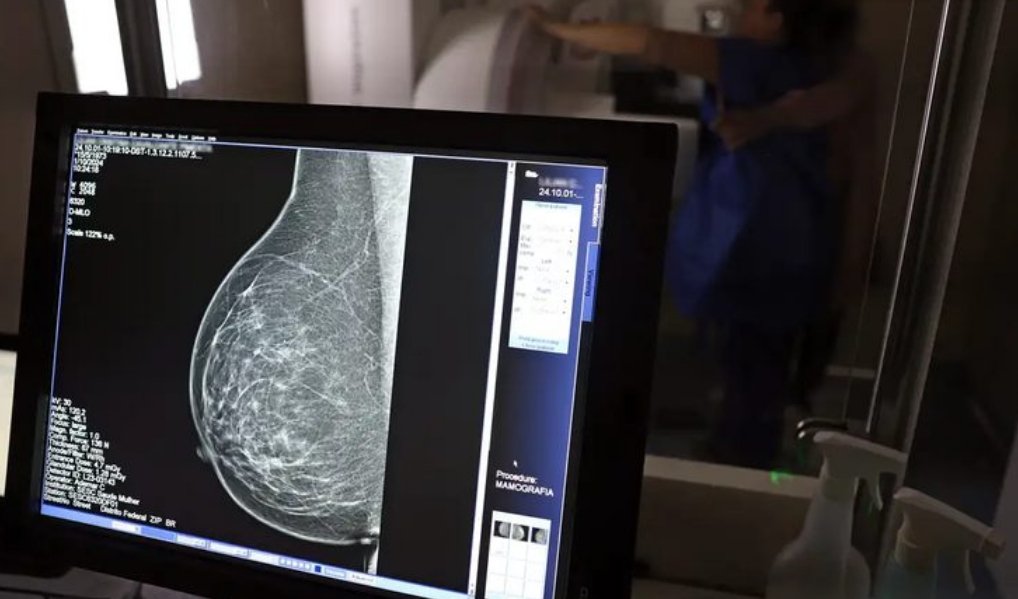

Foi publicada no Diário Oficial da União desta sexta-feira, 19 de dezembro, a Lei nº 15.284 , que fortalece o acesso das mulheres ao exame de mamografia fornecido pelo Sistema Único de Saúde (SUS). A partir de agora, o procedimento é garantido a mulheres a partir dos 40 anos de idade. Anteriormente, a idade em que o atendimento era oferecido, salvo casos especiais, era 50 anos.

A garantia ao exame se dará mesmo que as mulheres não apresentem sinais ou sintomas de câncer. A faixa etária dos 40 aos 49 anos concentra 23% dos casos da doença e a detecção precoce aumenta as chances de cura.

Em 2024, o Sistema Único de Saúde (SUS) realizou aproximadamente 4 milhões de mamografias para rastreamento e 376,7 mil exames diagnósticos. Esses números refletem a manutenção de uma ampla cobertura no país, reforçando a importância do rastreamento e do diagnóstico precoce para salvar vidas e garantir mais qualidade na atenção à saúde das mulheres.